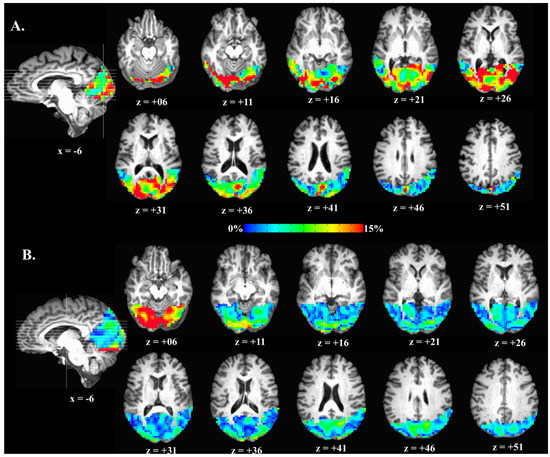

3.3. Group Comparisons on Visual Task cfMRI Measures

3.4. Within-Sample Classification Analyses